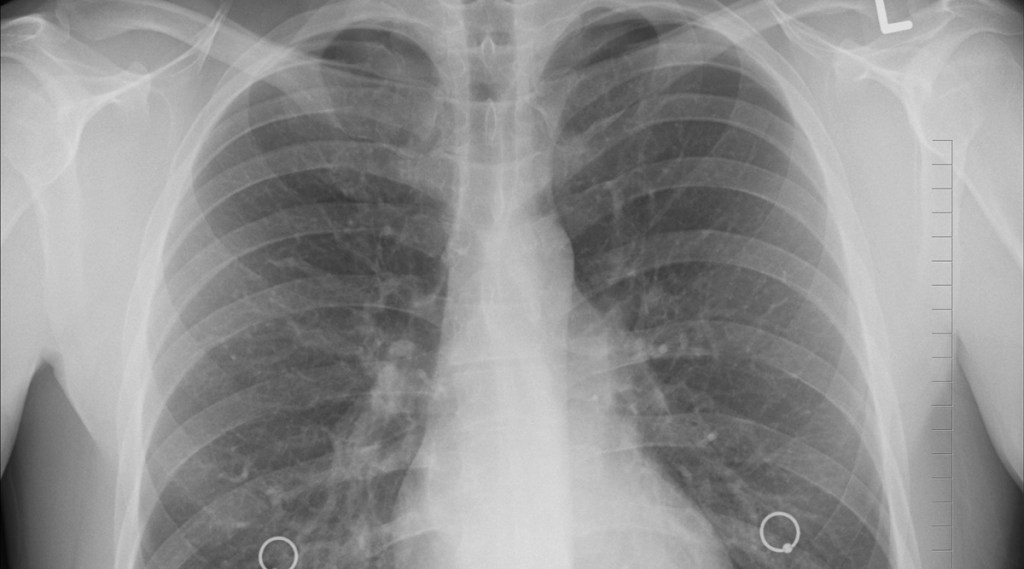

Today, November 16, is observed as World Chronic Obstructive Pulmonary Disease (COPD) Day and so I would like to share my perspective about how we can effectively manage this ailment. COPD is a progressive illness that includes the conditions of emphysema and chronic bronchitis. Patients generally have difficulty in breathing and experience symptoms that can have a negative impact on their quality of life. Now is the right time for us to take a step back, know about common symptoms of COPD like shortness of breath (dyspnea), coughing (especially with sputum production), constant fatigue, frequent respiratory infections and finally understand how to manage COPD to live a healthy life.

From a medical perspective, we need to focus on Disease Awareness, Diagnosis, Treatment and Adherence. While a lot of us are aware about respiratory diseases like asthma and pneumonia, COPD has been a silent killer for a long time. There is an urgent need for people to know more about COPD, from its causes to its symptoms and finally to its management. A primary route for treating COPD is the use of inhaler devices, where it is imperative for Doctors to emphasize on correct usage of these inhalers. To tackle this issue, Lupin has launched JAI (Joint Airways Initiative), the first digital platform for educating respiratory patients on correct inhalation techniques with an objective to improve the adherence and better manage the disease.